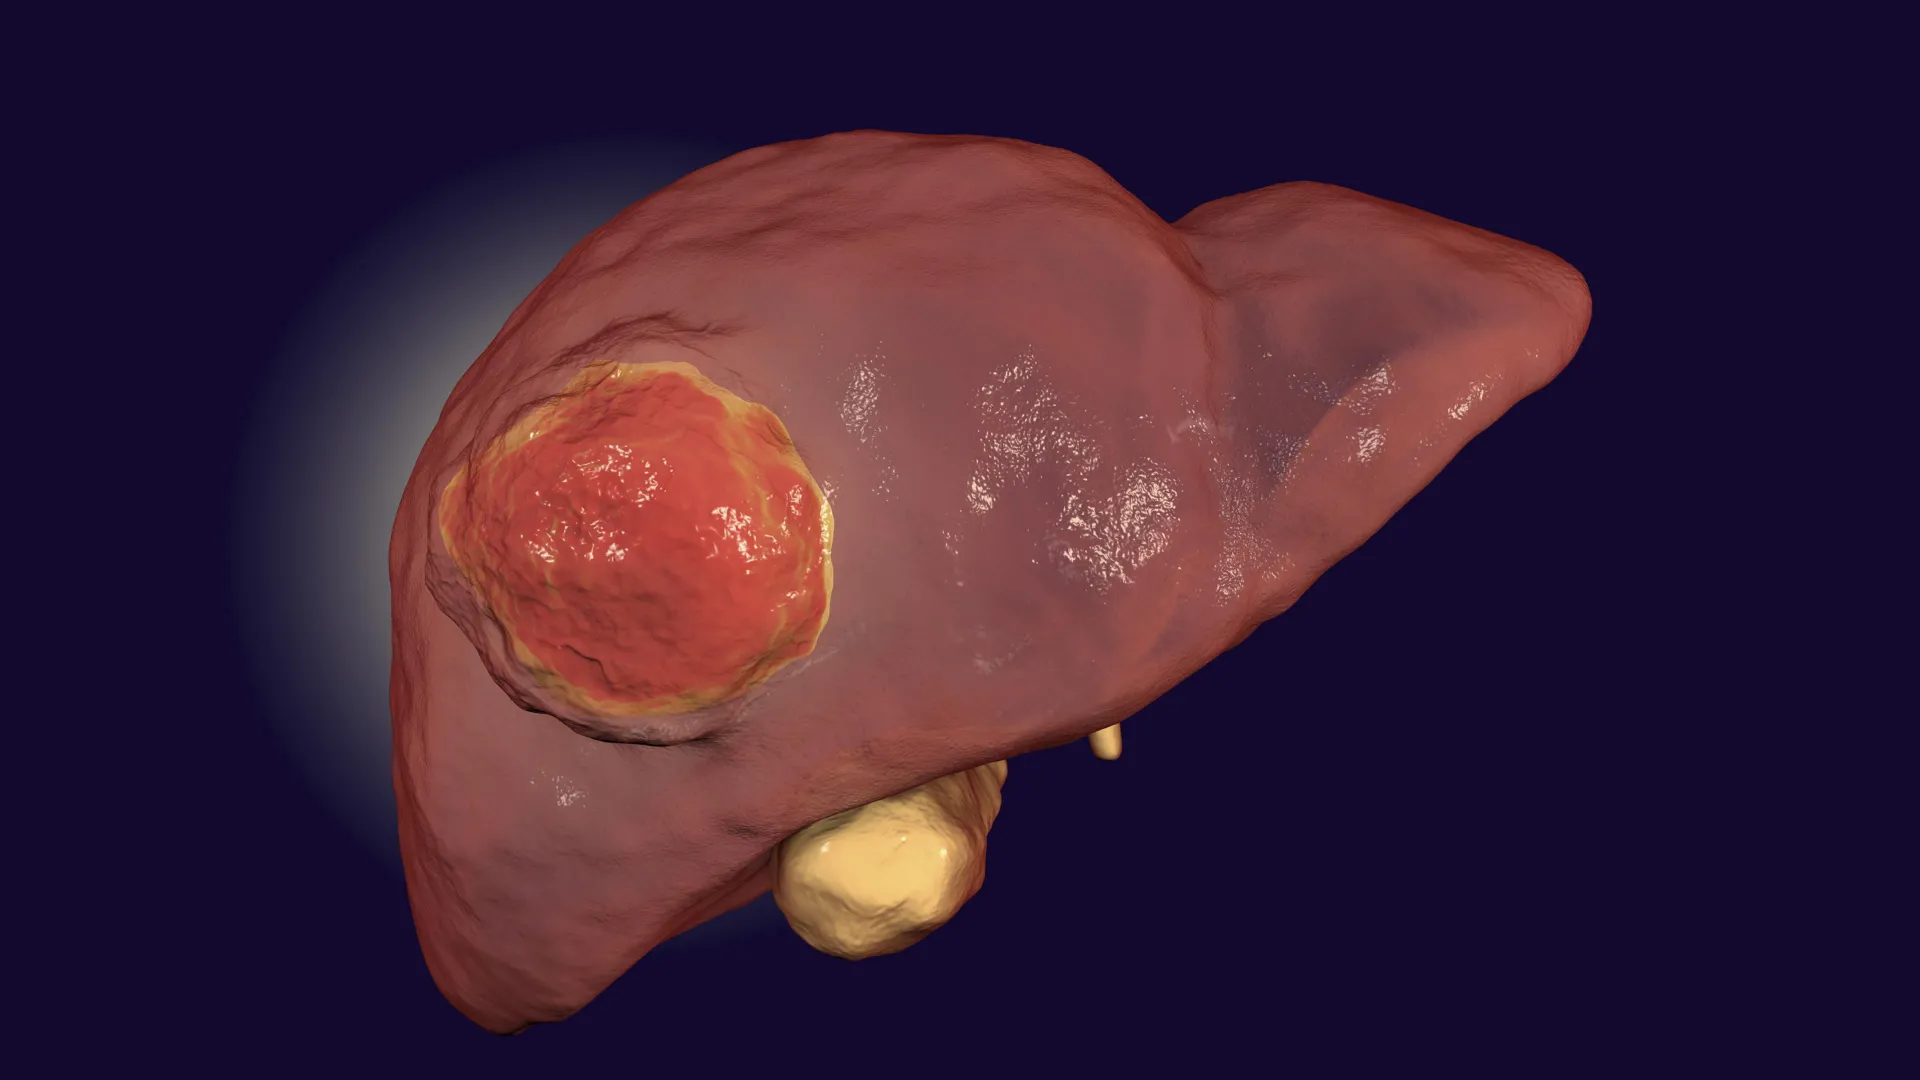

Hepatocellular carcinoma, a formidable and frequently lethal primary liver cancer, continues to pose a significant global health challenge, necessitating the exploration of novel prevention and therapeutic strategies. With a disheartening five-year survival rate hovering around 22% in the United States, and an anticipated 42,240 new diagnoses alongside 30,090 fatalities in 2025, according to projections from the American Cancer Society, the urgency for breakthrough research is undeniable. Compounding this crisis is the escalating prevalence of underlying liver pathologies that predispose individuals to malignancy. A substantial segment of the adult population, approximately one in four in the U.S., contends with fatty liver disease. This condition, alongside chronic viral hepatitis and excessive alcohol consumption, frequently culminates in cirrhosis, a severe scarring of the liver, which dramatically elevates the probability of developing liver cancer. In this context, recent groundbreaking research from Rutgers University offers a compelling new perspective, suggesting that a simple dietary adjustment—specifically, reducing protein intake—could potentially decelerate tumor progression or even mitigate cancer risk in individuals with compromised hepatic function.

The investigation, spearheaded by Rutgers researchers and published in the esteemed journal Science Advances, delves into the intricate metabolic pathways within a compromised liver. The findings illuminate how an organ struggling with its fundamental detoxification responsibilities can inadvertently foster an environment conducive to carcinogenesis. Central to this discovery is the role of ammonia, a compound that becomes toxic at elevated concentrations.

However, in individuals afflicted with liver disease or damage, the liver’s capacity to execute the urea cycle effectively is often impaired. This impairment leads to an accumulation of ammonia within the bloodstream and tissues, a condition known as hyperammonemia. Clinicians have long observed that liver cancer patients frequently exhibit deficiencies in the enzymatic machinery responsible for ammonia detoxification. This clinical correlation, noted for decades, presented a critical unanswered question: Was the observed impairment in ammonia metabolism merely a consequence of advanced cancer, or did the resulting ammonia buildup actively contribute to, or even drive, tumor growth? Resolving this long-standing scientific conundrum became the primary objective of the Rutgers team.

Further in-depth biochemical analysis by the research team unveiled the precise fate of this excess ammonia. They discovered that rather than being harmlessly converted into urea, the accumulating ammonia was being actively incorporated into fundamental molecular building blocks essential for cellular proliferation. Specifically, the team identified that ammonia was diverted into the synthesis of amino acids and nucleotides—molecules that are the very foundation upon which cancer cells construct new proteins and replicate their DNA, thereby facilitating their unchecked growth and multiplication. Dr. Zong succinctly articulated this critical metabolic shift, stating that the ammonia "goes into amino acids and nucleotides, both of which tumor cells depend on for growth." This revelation firmly established a direct mechanistic link, demonstrating that hyperammonemia is not merely a byproduct of liver cancer but a potent driver of its progression.